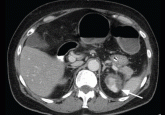

ArticleBilateral adrenal massesAuthor:Sima Saberi, MDPublish date: December 1, 2012In a woman with a thrombus in the aorta, imaging reveals bilateral high-density adrenal masses. What is the diagnosis?Read More